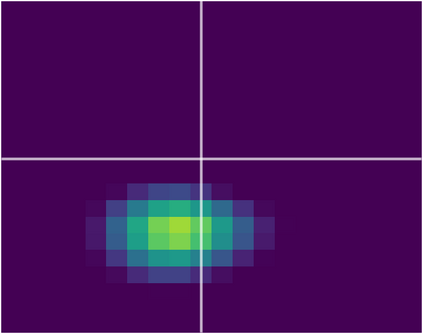

Various imaging modalities allow for time-dependent image reconstructions from measurements where its acquisition also has a time-dependent nature. Magnetic particle imaging (MPI) falls into this class of imaging modalities and it thus also provides a dynamic inverse problem. Without proper consideration of the dynamic behavior, motion artifacts in the reconstruction become an issue. More sophisticated methods need to be developed and applied to the reconstruction of the time-dependent sequences of images. In this context, we investigate the incorporation of motion priors in terms of certain flow-parameter-dependent PDEs in the reconstruction process of time-dependent 3D images in magnetic particle imaging. The present work comprises the method development for a general 3D+time setting for time-dependent linear forward operators, analytical investigation of necessary properties in the MPI forward operator, modeling aspects in dynamic MPI, and extensive numerical experiments on 3D+time imaging including simulated data as well as measurements from a rotation phantom and in-vivo data from a mouse.